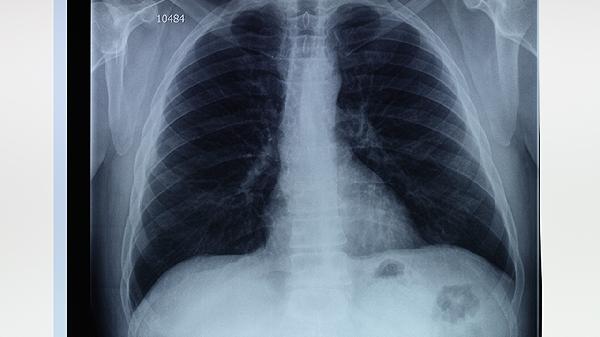

肺大泡患者可通过戒烟、药物治疗、氧疗、肺康复训练、手术治疗等方式改善病情。肺大泡通常由慢性阻塞性肺疾病、长期吸烟、肺部感染等因素引起,表现为呼吸困难、咳嗽等症状。

对于直径超过3厘米的肺大泡或反复气胸发作患者,胸腔镜下肺大泡切除术是首选术式。术后需加强呼吸道管理,预防肺不张和感染。巨大肺大泡或弥漫性病变者可能需肺减容术,但需严格评估手术指征。

肺大泡患者应保持居住环境空气流通,避免剧烈运动和高压环境。饮食上多摄入高蛋白食物如鱼肉、鸡蛋,适量补充维生素C促进组织修复。冬季注意保暖防感冒,每年接种流感疫苗和肺炎疫苗。定期复查胸部CT监测肺大泡变化,出现突发胸痛或呼吸困难加重需立即就医。